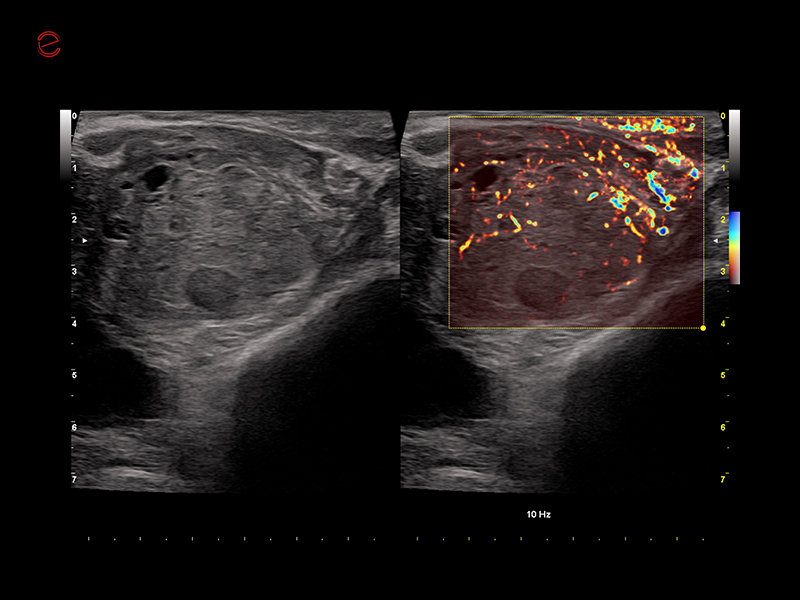

microV shows vascularization and improves the visualization of slow blood flow in tiny vessels.

An adaptive algorithm identifies the blood flow signals and separates them from background tissue and motion artefacts. By eliminating background noise, microV technology enables an advanced hemodynamic evaluation with maximum sensitivity and spatial resolution.

microV to study the micro-vascularization of the suspicious area